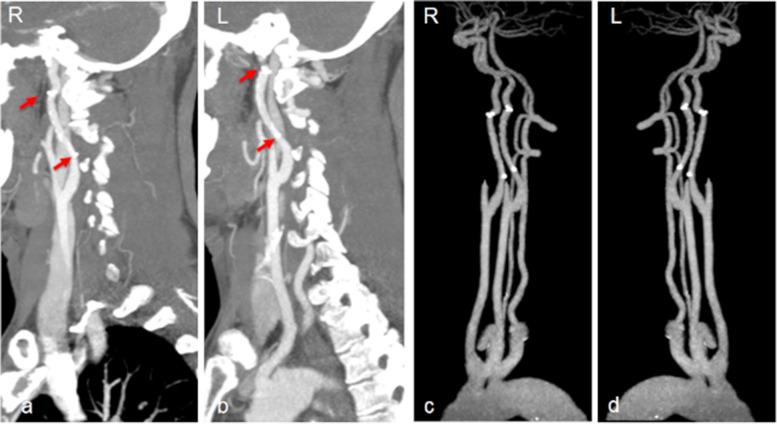

Primary stent implantation for bilateral spontaneous cervical ICA dissections with hypoperfusion after 72 h from onset: a case report.

A bilateral spontaneous cICADs with hypoperfusion-related AIS after 72 h from the onset was presented herein. The patient responded well to primary Solitaire stent detachment at the critical flow-limiting site.

Primary stent implantation at the critical flow-limiting site rather than covering the entire dissection may be a therapeutic option in spontaneous cICAD complicated with cerebral hypoperfusion. The Solitaire stent may be a good choice at the acute and subacute stages of cICAD.